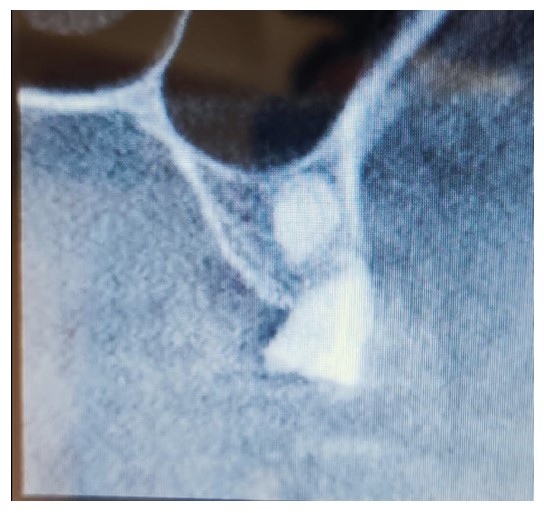

A female patient in her 50s sought rehabilitation for the posterior maxilla with a fixed implant-supported prosthesis. Clinical examination revealed missing maxillary premolars and molars, with residual roots in the maxillary first molar region. OPG and CBCT scans indicated sufficient bone for implant placement in the premolar region, and residual roots were noted in the molar region (Figs. 5 and 6).

Periapical view of the maxillary molar region showing unrestorable roots, as well as a radiopaque lesion on the periapical plane that was not noticed during the preoperative radiograph.

Preoperative scan showing the location of the lesion noted when reviewing scans after implant failure.